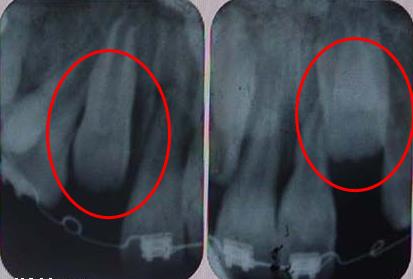

3、埋伏牙長期存在,如果會(hui) 造成鄰牙牙根破壞以及牙槽骨吸收的話,建議盡早拔除比較好。

4、有的埋伏牙可能暫時沒什麽(me) 事情,可以先不用管。但是它有發展成為(wei) 囊腫破壞鄰牙的可能,一定要定期觀察埋伏牙的情況。